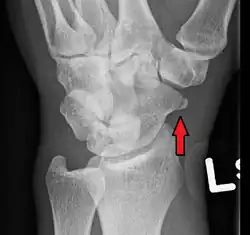

-

A subtle scaphoid fracture -